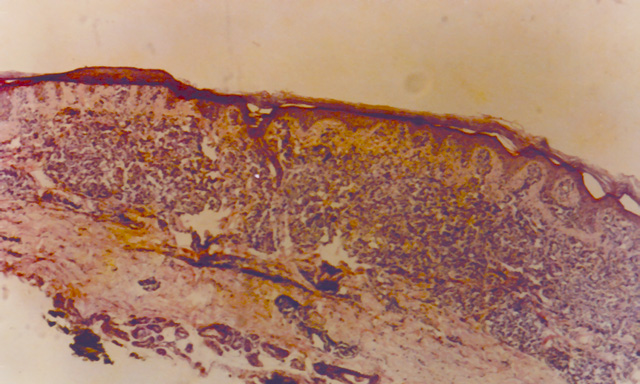

La biospia de piel presenta infiltración linfocitaria de caracter epidermotropa, compuesta por linfocitos pequeños que alternan con formas pleomórficas. Se observa exocitosis y formación de lesiones similares a los Pesudoabcesos de Pautrier, observables en los casos de Micosis Fungoides. Realiándose el diagnóstico de Linfoma T cutáneo de tipo ATL.

Fig.1: ATLL, Biopsia Cutánea. H-E - <div style=fiogf49gjkf0dFormación de lesiones tipo Pseudo-abcesos de Pautrier.">

Formación de lesiones tipo Pseudo-abcesos de Pautrier.